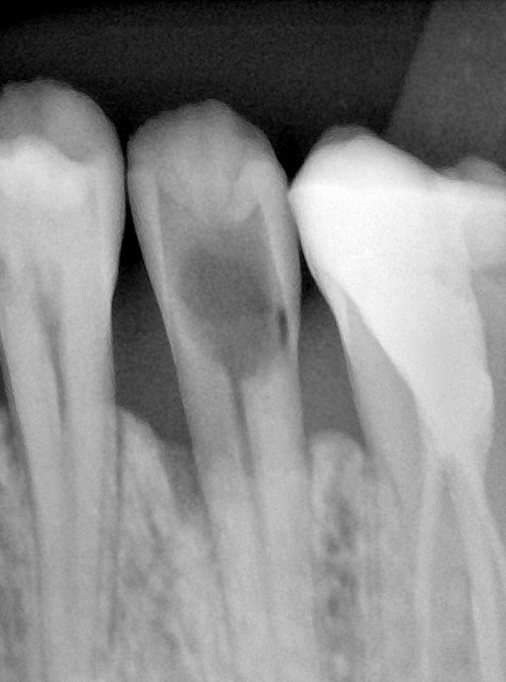

CR/DR 牙齿分割阶段记录

当前进展

- 完成了 CR/DR 牙齿相关分割训练

- 当前结果已经达到阶段预期,但仍有细节问题需要继续处理

相关测试

遇到的问题

- 训练过程中出现过 mask 下移问题

- 部分结果会出现 box 填充异常

- mask 边缘仍然有比较明显的锯齿感